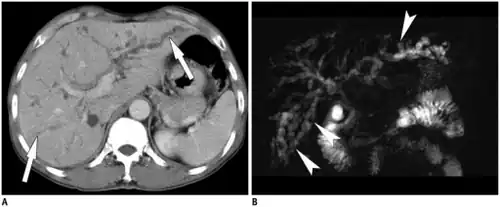

Typical imaging features center around imaging of the liver with CT, ultrasound, or MRI for detection of primary biliary cirrhosis. Traits that raise suspicion for the infection include intra- and extrahepatic dilatation and structures with intraductal pigmented stones, usually in the absence of gallstones and with regions of segmental liver atrophy, particularly the lateral aspect of the left hepatic lobe. Also, reduced arborization of peripheral ducts is seen. A full 5% of chronic infections go on to develop cholangiocarcinoma.[28]